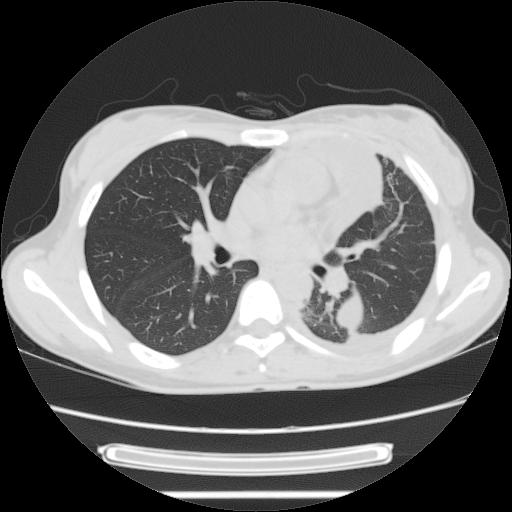

女,29岁,胸部不适,在外院胸片提示胸腔积液,到我院ct检查。

肺窗:

左肺上叶不张,左侧胸水,叶间裂积液,纵隔淋巴结,脾脏钙化,考虑左肺上叶支气管内膜结核,结核性胸膜炎,脾结核

考虑:1.两肺tb;2.左侧胸膜炎、胸腔积液。

考虑两肺结核,左侧包裹性积液,叶间积液。

右肺多发结节。左胸腔多发包裹性积液。

左肺上叶不张,左侧胸水,叶间裂积液,纵隔淋巴结,脾脏钙化,考虑左肺上叶支气管内膜结核,结核性胸膜炎,脾结核。支持!